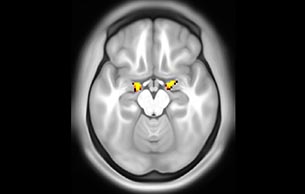

Imaging was performed using Ingenia 3T CX with a 32ch dS Head coil, TR 1.6 sec, TE 35 ms, voxel size 3.1 x 3.1 x 3.1 mm, 46 slices and Multiband SENSE factor 2. Image provided by Dr. Gispert

Default mode network as discovered by resting state fMRI in one participant of the ALFA cohort [7]. rs-fMRI allows us to find networks of brain regions with highly correlated activity and sustaining distinct brain functions. The default mode network (in warm color scale) is active when the brain is focused on introspective thinking and has been shown to be altered in Alzheimer’s. Interestingly, brain areas of this network are known to show abnormal levels of one of the pathological hallmarks of Alzheimer’s (b-amyloid deposition) in preclinical stages. We want to better understand the alterations of these brain networks in preclinical stages of Alzheimer's and explore their potential use as biomarkers.